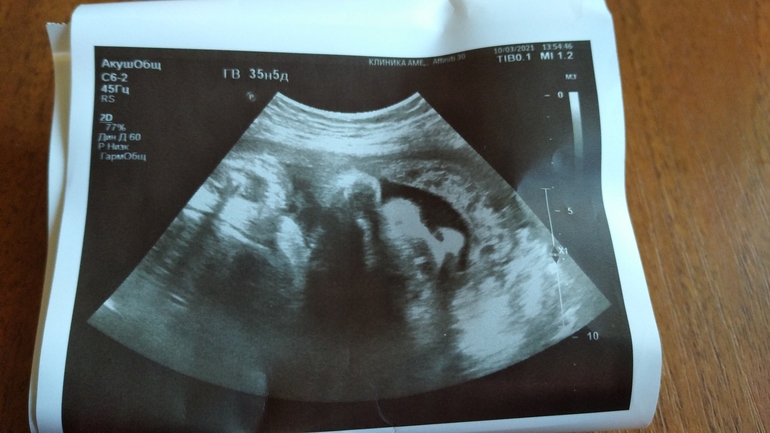

УЗИ, КТГ, доплерКак же я счастлива!🤗😁 Не передать словами. Не выдержала и сходила на УЗИ, думаю как раз после болезни проверю.

Малышка в головном предлежании! Ура!!! Когда перевернулась непонятно, главное чтоб там и оставалась. Кстати, сказали носить бандаж, он чё правда поможет чтоб она уже улеглась и не ворочалась?

Вес сегодня 2500, лёгкие 2 степени, так что уже не страшно если захочет выйти пораньше. Но я не хочу раньше апреля- сказали нельзя))) у сына 30 марта ДР, сказал чтоб сидела аж до апреля. Думаю мы с доцей договорились☺️